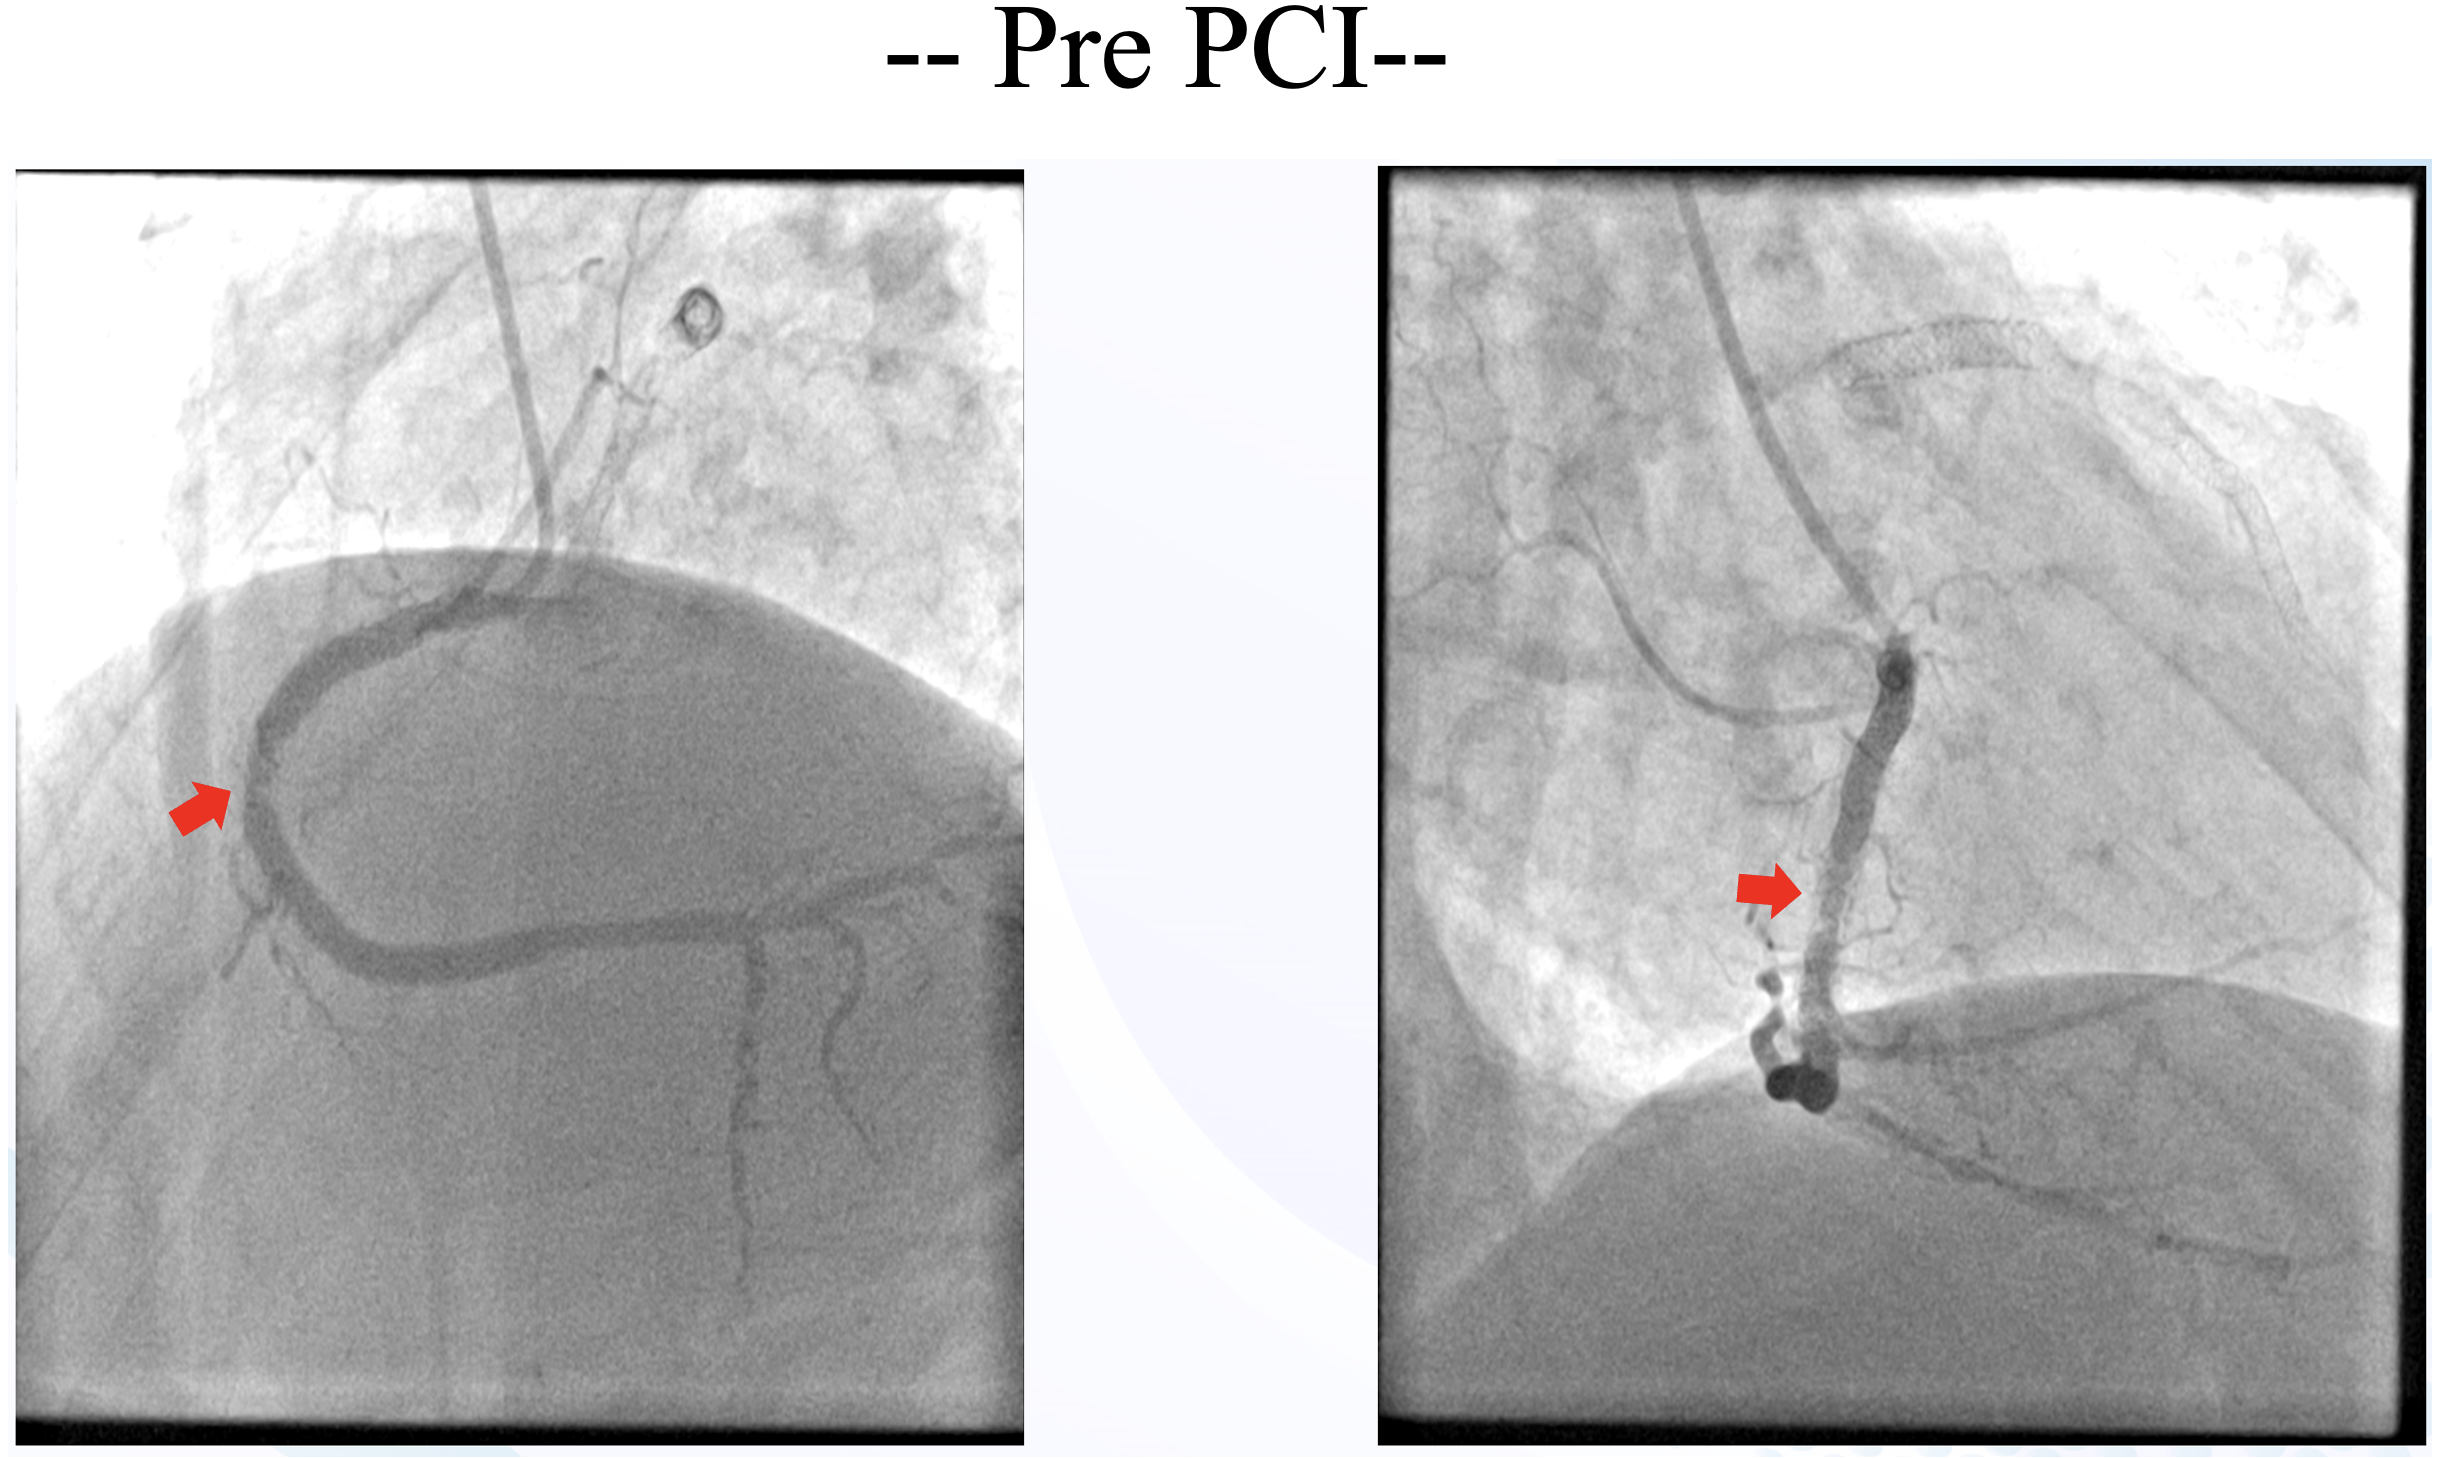

Just 6 months after last PCI, the patient was readmitted back with NSTEMI. Left coronary angiography showed patent LAD stent and diffuse non-significant stenosis of the LCx (consistent with prior angiography). Right coronary angiography showed significant recurrent In-stent restenosis (ISR) in mid RCA.

Right radial access was obtained, right coronary ostium was selectively cannulated with 6F Hockey stick guiding catheter. Runthrough NS wire was advanced into the distal RCA. Optical coherence tomography (OCT) using saline was performed to minimize the risk of worsening kidney function. OCT revealed concentric calcification with both eruptive and non-eruptive calcific nodules protruding through multiple stent struts, resulting in stent underexpansion (MSA 3.67 mm2). Red thrombus was also present around the lesion. Predilatation with a 3.5 x15 mm cutting balloon using controlled, prolonged inflation up to 12 atm was attempted; a persistent ¡°waist¡± was observed, indicating inadequate lesion modification. For better lesion preparation, then we performed Intravascular Lithotripsy (IVL) using Shockwave 3.5 x12 mm C2 IVL balloon and 80 pulses were delivered at mid RCA. IVL balloon expansion was satisfactory at 6 atm, and no residual waist observed. OCT after IVL showed calcium fractures at multiple sites and compression of protruding calcifications, with increased luminal area. Further dilation was performed with 3.5 x 15 mm NC balloon. This was followed by delivery of a 4.0 x 20 mm paclitaxel-eluting balloon (DEB) at the mid RCA for 60 seconds. Final angiography and OCT evaluation showed excellent results, with MSA improved from 3.67 mm©÷ to 7.71 mm©÷.